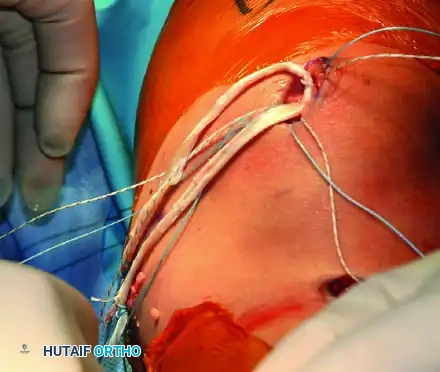

Graft Passage, Tensioning, and Fixation

- Graft Passage: Pass the whipstitched tails of the graft through the extrasynovial soft tissue tunnel to the femoral incision.

Figure 47-15D: Graft tails passed through the extrasynovial soft tissue tunnel toward the femoral footprint.

- Tensioning: Pull the graft taut into the femoral tunnel. Flex the knee to 30 degrees. Apply a lateral translation force to the patella. The graft should be tensioned to allow one to two quadrants of lateral passive glide.

- Femoral Fixation: Once physiological tension is determined, mark the graft at the tunnel aperture. Cut the excess graft 20 mm distal to this mark. Place absorbable whip sutures in the new tails, pass them through the eyelet of a Beath pin, and pull them out the lateral aspect of the thigh. Secure the graft in the femoral tunnel using a biocomposite interference screw that is 1 mm smaller than the tunnel diameter.